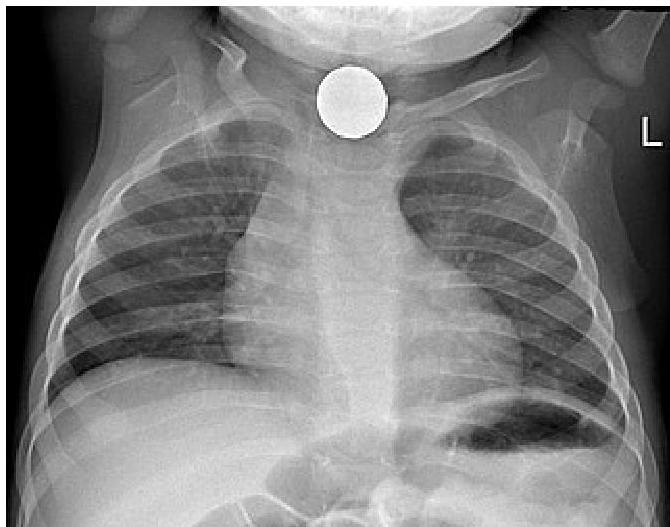

Left: Focal pneumonia in lower right lung lobe due to aspiration and airway obstruction. Right: Coin in the esophagus.

Foreign body aspiration of a coin in the esophagus